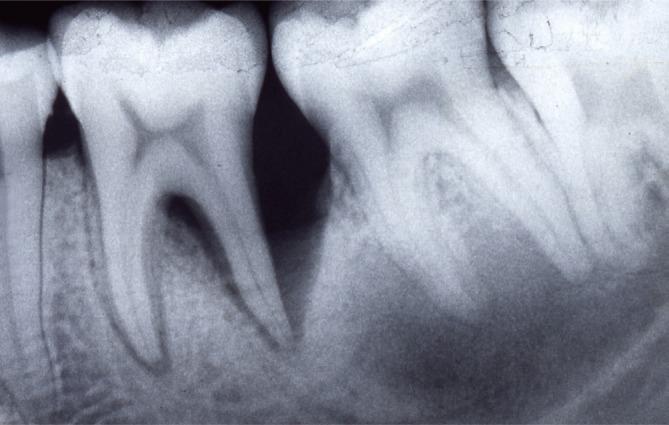

Seven patients with 266 periodontal sites were examined. A significant difference was found between values, reported as medians with interquartile ranges, for PD at baseline (7.94 [7.33-8.19] mm) and both re-evaluation (4.33 [3.63-5.08] mm) and posttreatment (3.54 [3.33-4.11] mm) values (P=0.002). A significant difference was also found between values for CAL at baseline (9.02 [7.5-9.2] mm) and both re-evaluation (6.55 [6.30-6.87] mm) and posttreatment (6.45 [5.70-6.61] mm) (P=0.002). Inflammation was resolved and angular bone defects were repaired in all cases.

These therapeutic results suggest that this form of periodontitis could have positive outcomes after nonsurgical periodontal treatment. The reparative potential of tissue affected by severe aggressive periodontitis should encourage clinicians to save apparently hopeless teeth in cases of this form of periodontitis.